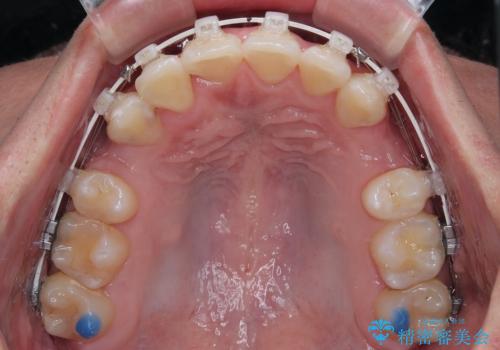

上下左右の第一小臼歯を抜歯してスペースを確保する計画を立てました。

矯正装置には白いプラスチックブラケットと白いコーティングワイヤーを使用し、見た目にも配慮した治療を行いました。